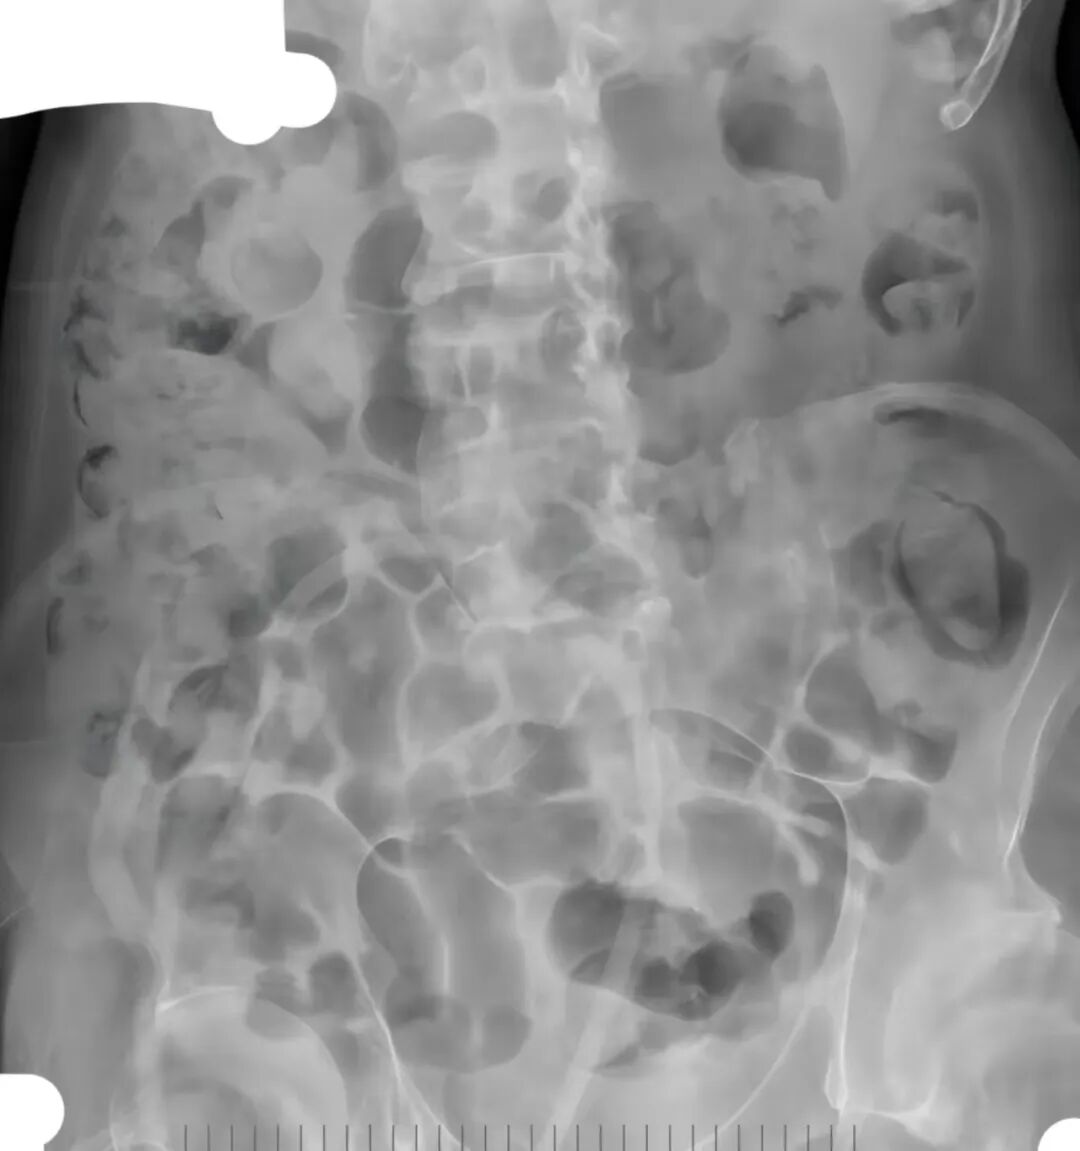

(左图为术前   右图为术后腹部平片)

术中,患者膀胱腔内填满结石,大小不一,大者约3.0cm,小的约1.0cm,整个膀胱腔内全是结石。

从内镜下看密密麻麻结石,泌尿外科团队45分钟的“与石搏斗”手术在镜下未见结石残留、膀胱粘膜无明显出血,持续膀胱冲洗液清亮后宣布结束。